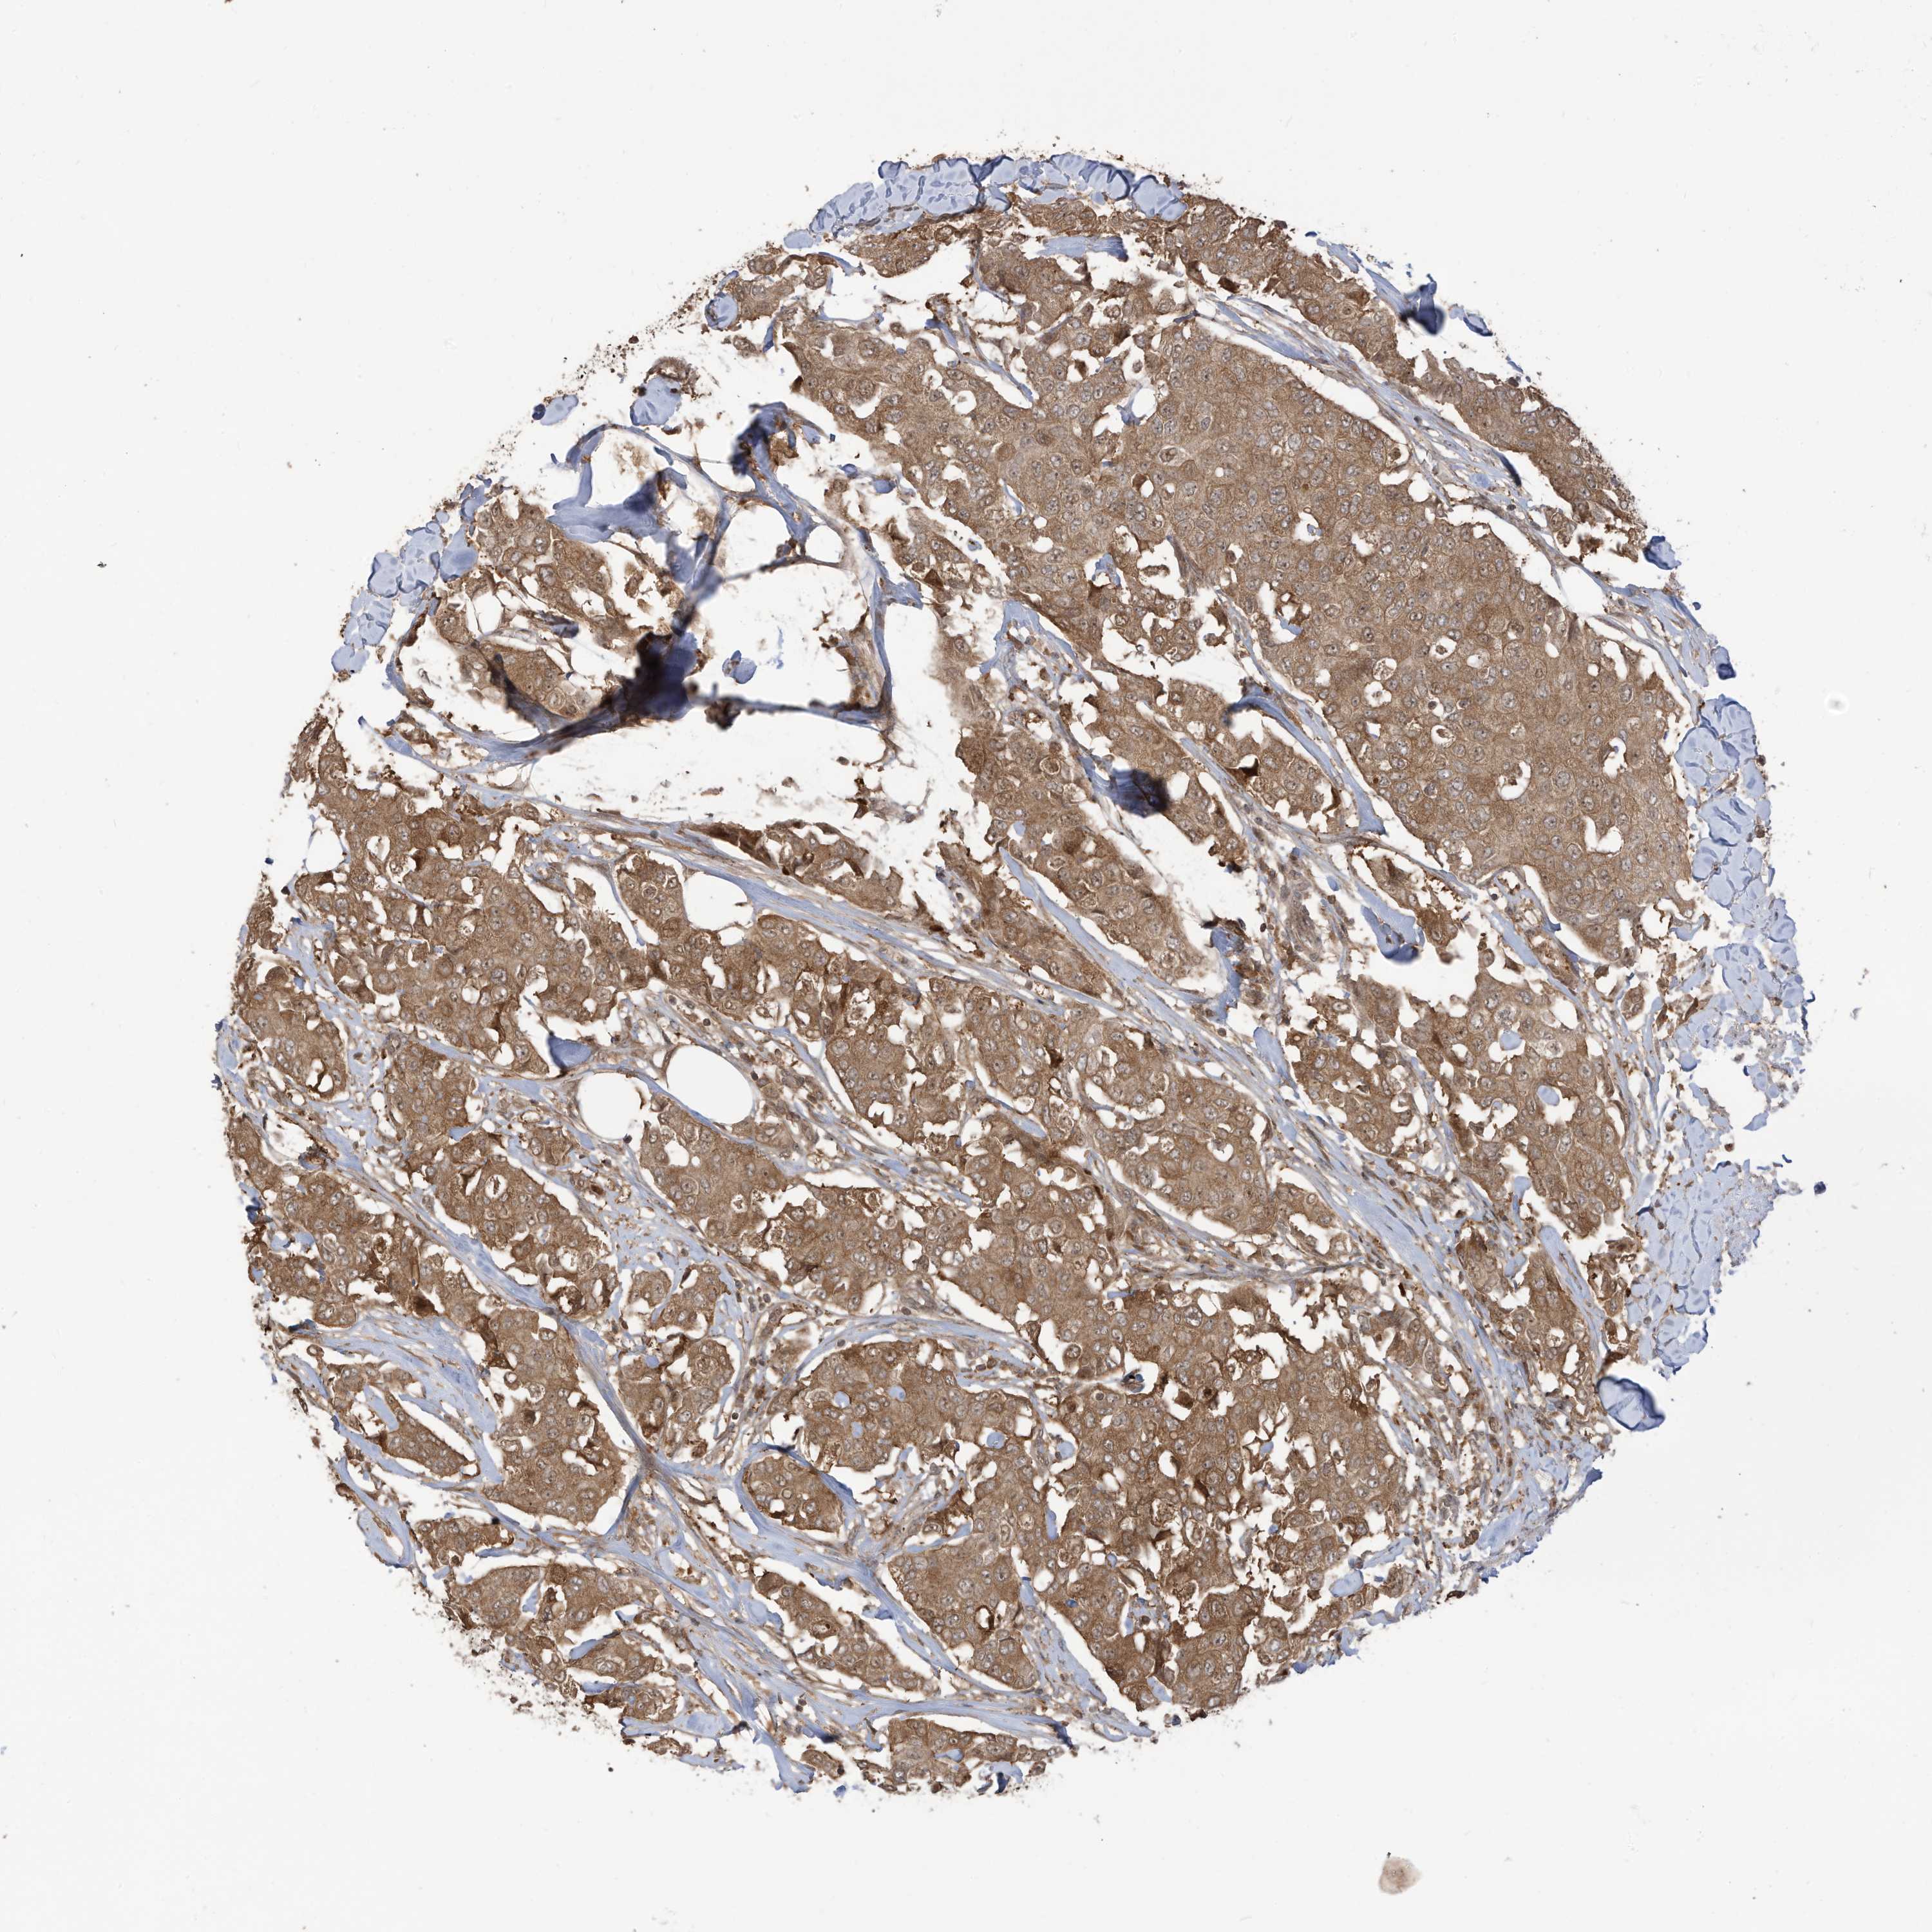

BRCA TCGA BRCA VALIDATION PROTEIN EXPRESSION

Breast cancer

Human cancer